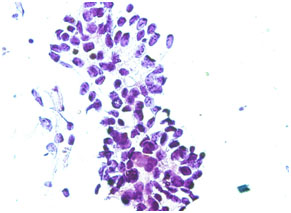

Figure 1. Photomicrograph of imprint cytology of adenocarcinoma (Papanicolaou stain, x40).